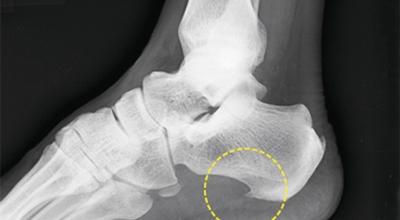

족저 근막이란 발가락 시작지점부터 발뒤꿈치뼈까지 발바닥 전체를 감싸고 있는 두꺼운 막을 말합니다. 족저 근막은 발바닥 아치를 지속시켜 발바닥이 지면을 내딛음으로써 발생하는 충격을 흡수하는 중요한 역할을 수행하고 있답니다. 이 족저 근막에 일차적으로 서서히 조직 손상이 일어나고 계속적인 활동으로 말미암아 염증이 커지면서 발 뒤꿈치 부근 통증을 일으키게 되는데 염증은 무리하고 반복적인 동작, 많은 사용으로 마찰에 의해 발생합니다.

족저 근막염은 염증에 의한 손상 및 통증을 유발하는 질환인데요 족저 근막염 증상은 일반적인 발뒤꿈치 통증 하글런드 병변의 기형으로 알려져 있으고 아킬레스 건과 관련이 깊다고 합니다. 특히 근육이 덜 풀린 아침 시간 대는 보행 시 날카롭고 바늘로 찌르는 듯한 심한 통증을 느끼게 된다고 합니다. 하지만 아침 시간 대를 지나 오후에 접어들면서 어느 정도 통증은 서서히 감소하기 시작한다고 하는데요 초기 증상이 나타난다면 꼭 전문의를 찾아 조기치료하는 것이 바람직합니다.